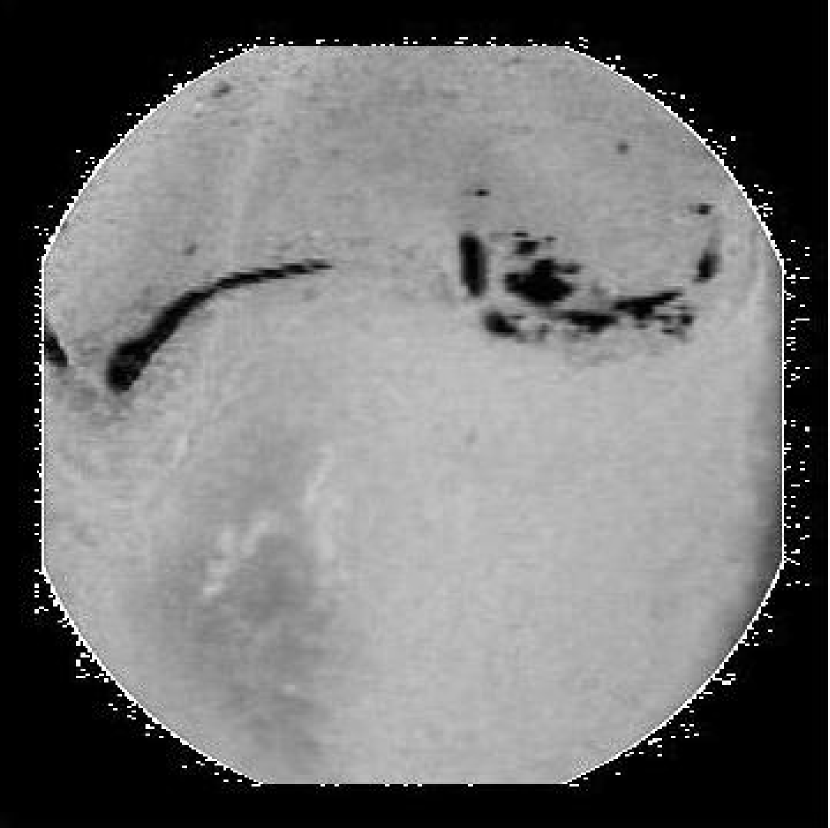

Refer to caption

(a) Original Image

(b) Annotation

(c) RoI selected of the ‘a’ component image

Figure 2: Selection of Region of Interest